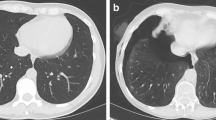

Representative cases of standard dose and ultralow dose CT are given in Figs. 5 and 6.

Representative transverse CT sections of the lung in a 75-year-old woman with a body mass index of 24.4 kg/m2 scanned with standard dose (A) at 100 kVp and 54 mAs (effective dose, 1.09 mSv; size-specific dose estimate, 3.13 mGy) and ultralow dose (B) at 100 kVp and 70 mAs (effective dose, 0.12 mSv; size-specific dose estimate, 0.34 mGy). The subsolid pulmonary nodule in the left lower lobe (arrow) was not detected by either of the reader in ultralow dose CT (i.e., false negative finding). Representative transverse CT sections of the lung in a 75-year-old woman with a body mass index of 42.8 kg/m2 scanned with standard dose (C) at 110 kVp and 142 mAs (effective dose, 4.13 mSv; size-specific dose estimate, 6.86 mGy) and ultralow dose (D) at 100 kVp and 70 mAs (effective dose, 0.13 mSv; size-specific dose estimate, 0.22 mGy). Note the markedly increased image noise in the ultralow dose CT scan. In spite of the image noise the solid pulmonary nodule in the left lower lobe was detected in ultralow dose CT by both readers (i.e., true positive finding)